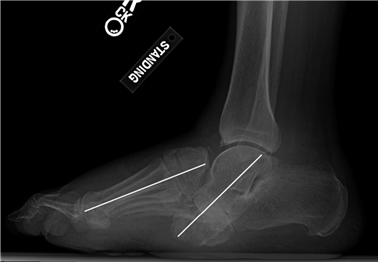

Weight-bearing anteroposterior (AP), lateral, and sesamoid axial radiographs are mandatory. On the AP view, the surgeon measures the Hallux Valgus Angle (HVA, normal < 15°), the Intermetatarsal Angle (IMA, normal < 9°), and the Distal Metatarsal Articular Angle (DMAA). The lateral view is scrutinized for Meary's angle (talo-first metatarsal angle) to identify midfoot collapse, as well as the presence of dorsal osteophytes indicative of hallux rigidus. The sesamoid axial view is critical for assessing the degree of sesamoid subluxation and the integrity of the crista.

Clinical & Radiographic Imaging Archive